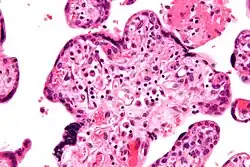

Micrograph of villitis of unknown etiology, a placental pathology associated with IUGR. H&E stain.